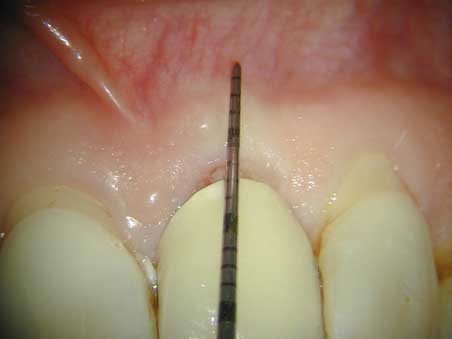

PA – Sonde prä OP: 6 mm Sondiertiefe Veröffentlicht 16. März 2009 am 452 × 339 in Seitenkanal PA – Sonde prä OP: 6 mm Sondiertiefe